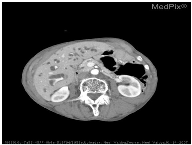

| Image | Category | Generated and Ground Truth Questions |

|---|---|---|

![]() | Organ | is this a typical liver? are these normal laughed kidneys? Is this a study of the brain? |